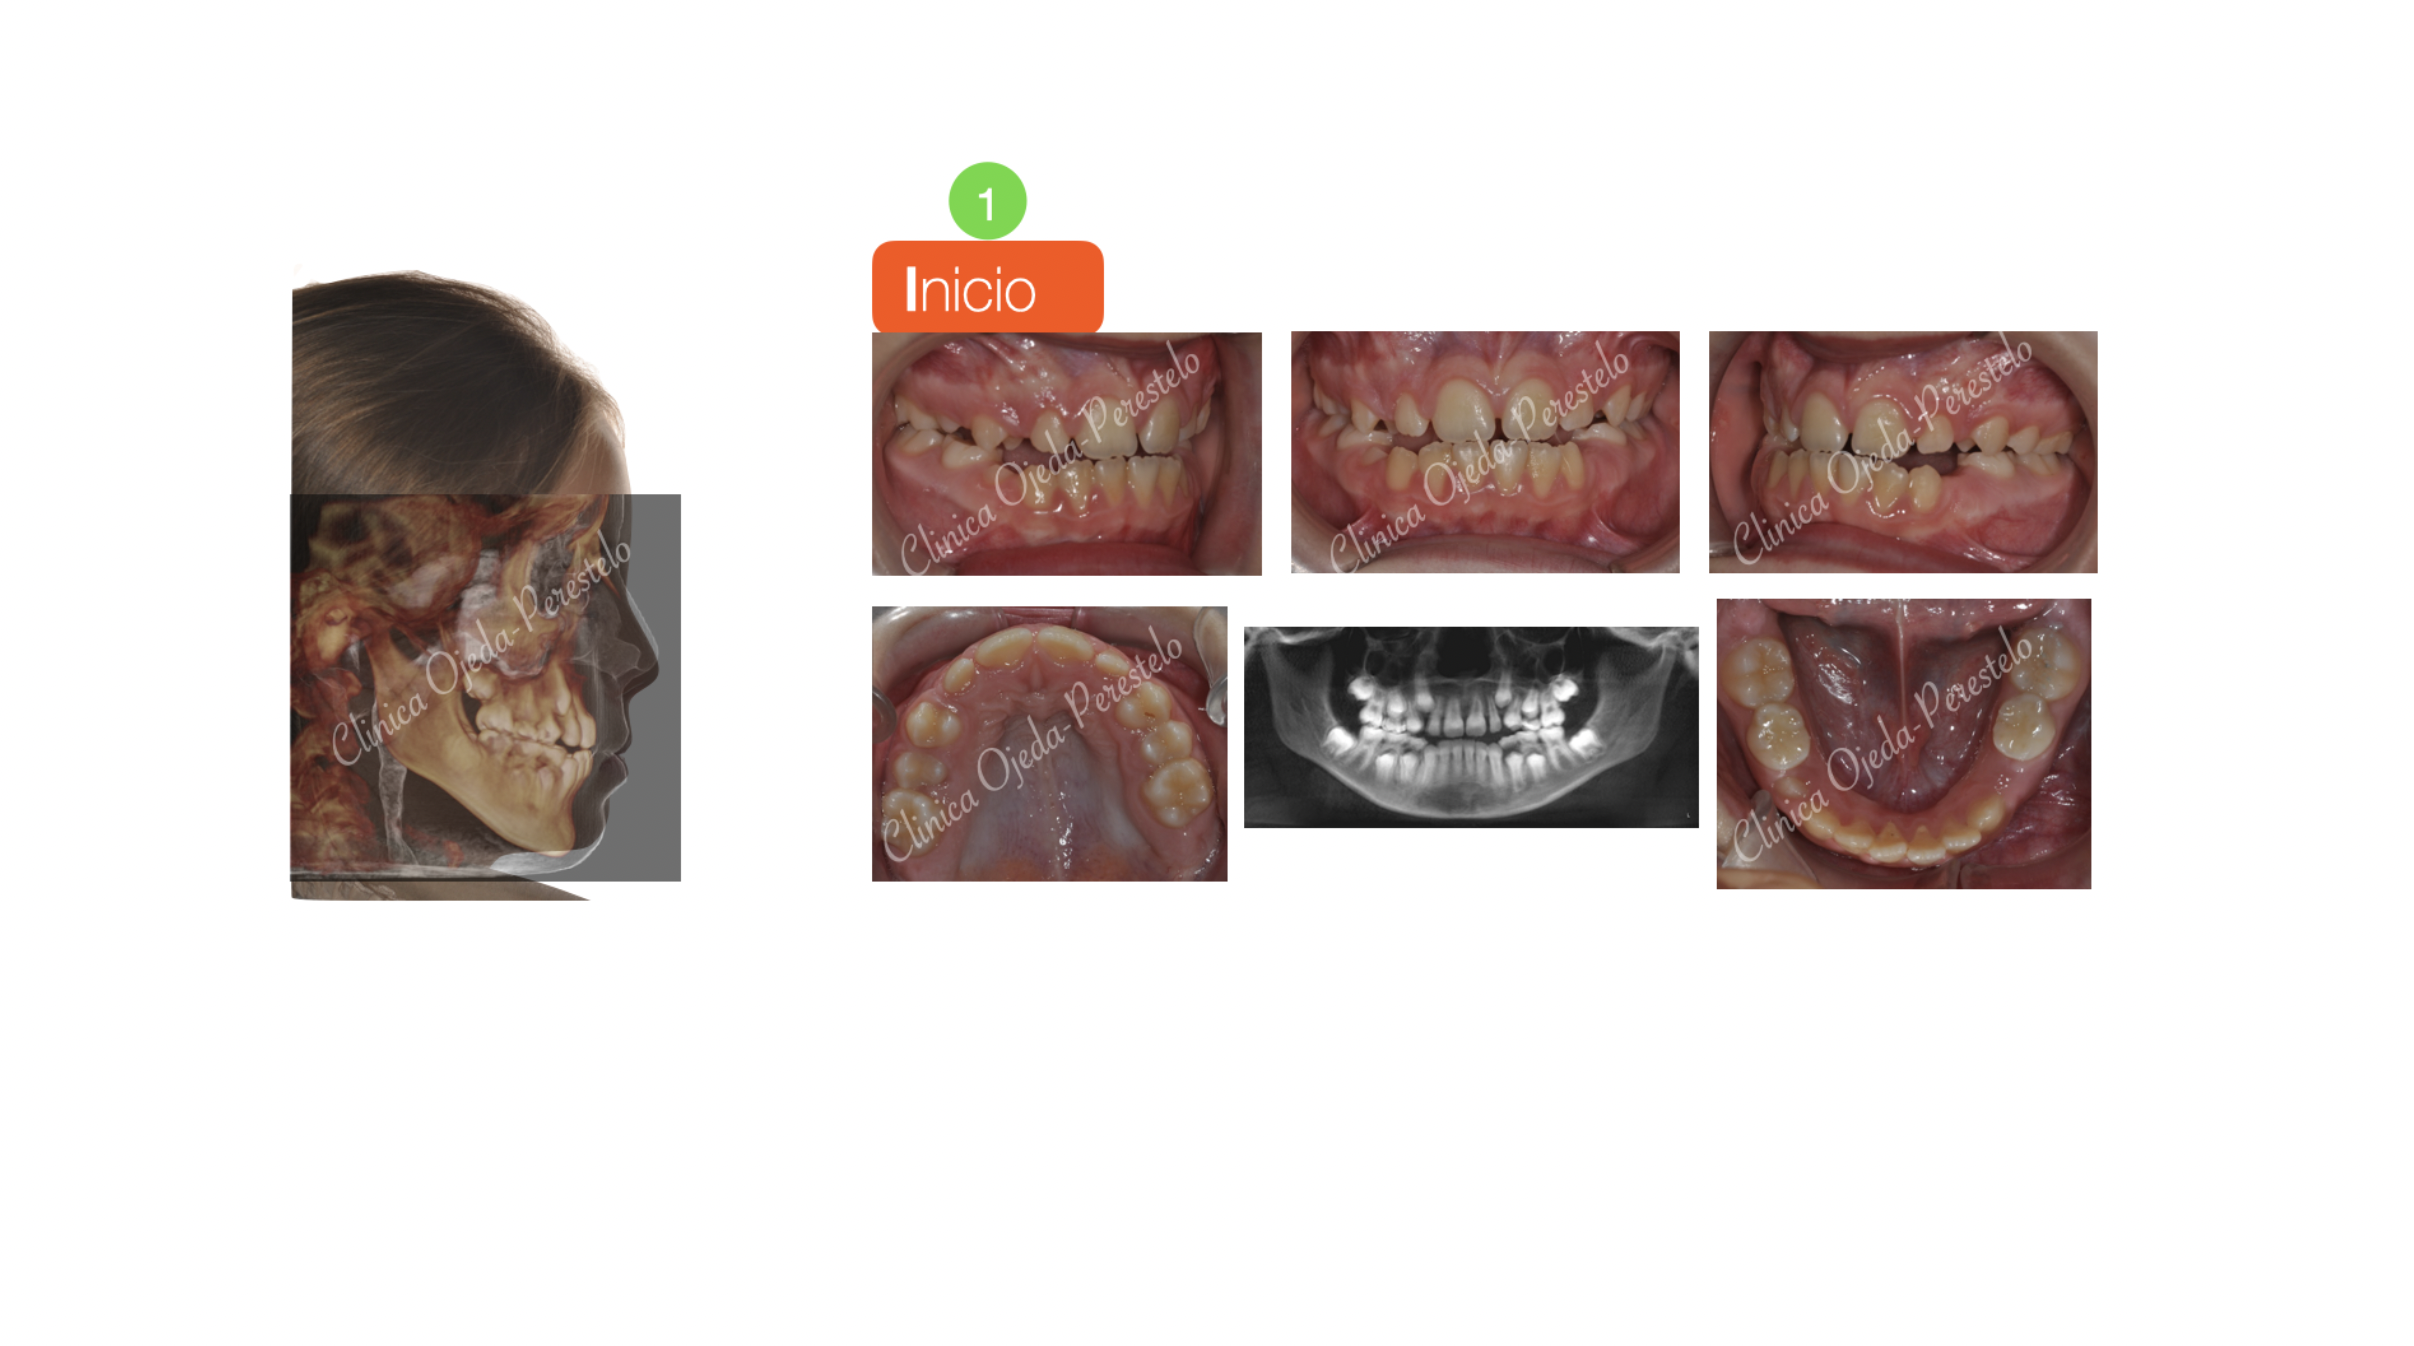

Clase III esquelética en dentición mixta

Paciente niña en dentición mixta y clase III esquelética tratado con Ortopedia Maxilar.

Se decidió combinar un Disyuntor Oseosoportado con una Máscara Facial ya que presentaba un déficit esquelético del Maxilar. El impacto facial alcanzado con esta estrategia ha sido relevante y equivalente al que observamos en una intervención quirúrgica del Maxilar (Cirugía ortognática Unimaxilar).

Además hemos observado la desaparición de sus ronquidos por el aumento de la Vía Aérea (51,08%) potenciado por la  Ortopedia practicada sobre el Maxilar Superior.